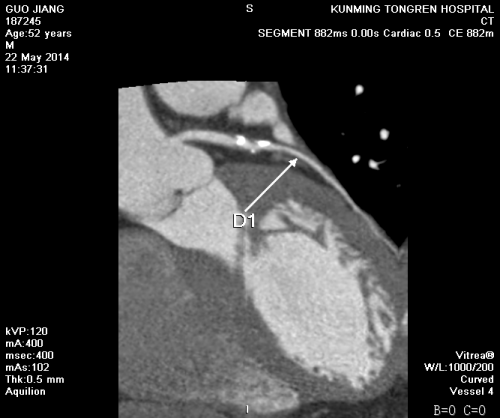

我院影像科冠状动脉CT造影片如下图: